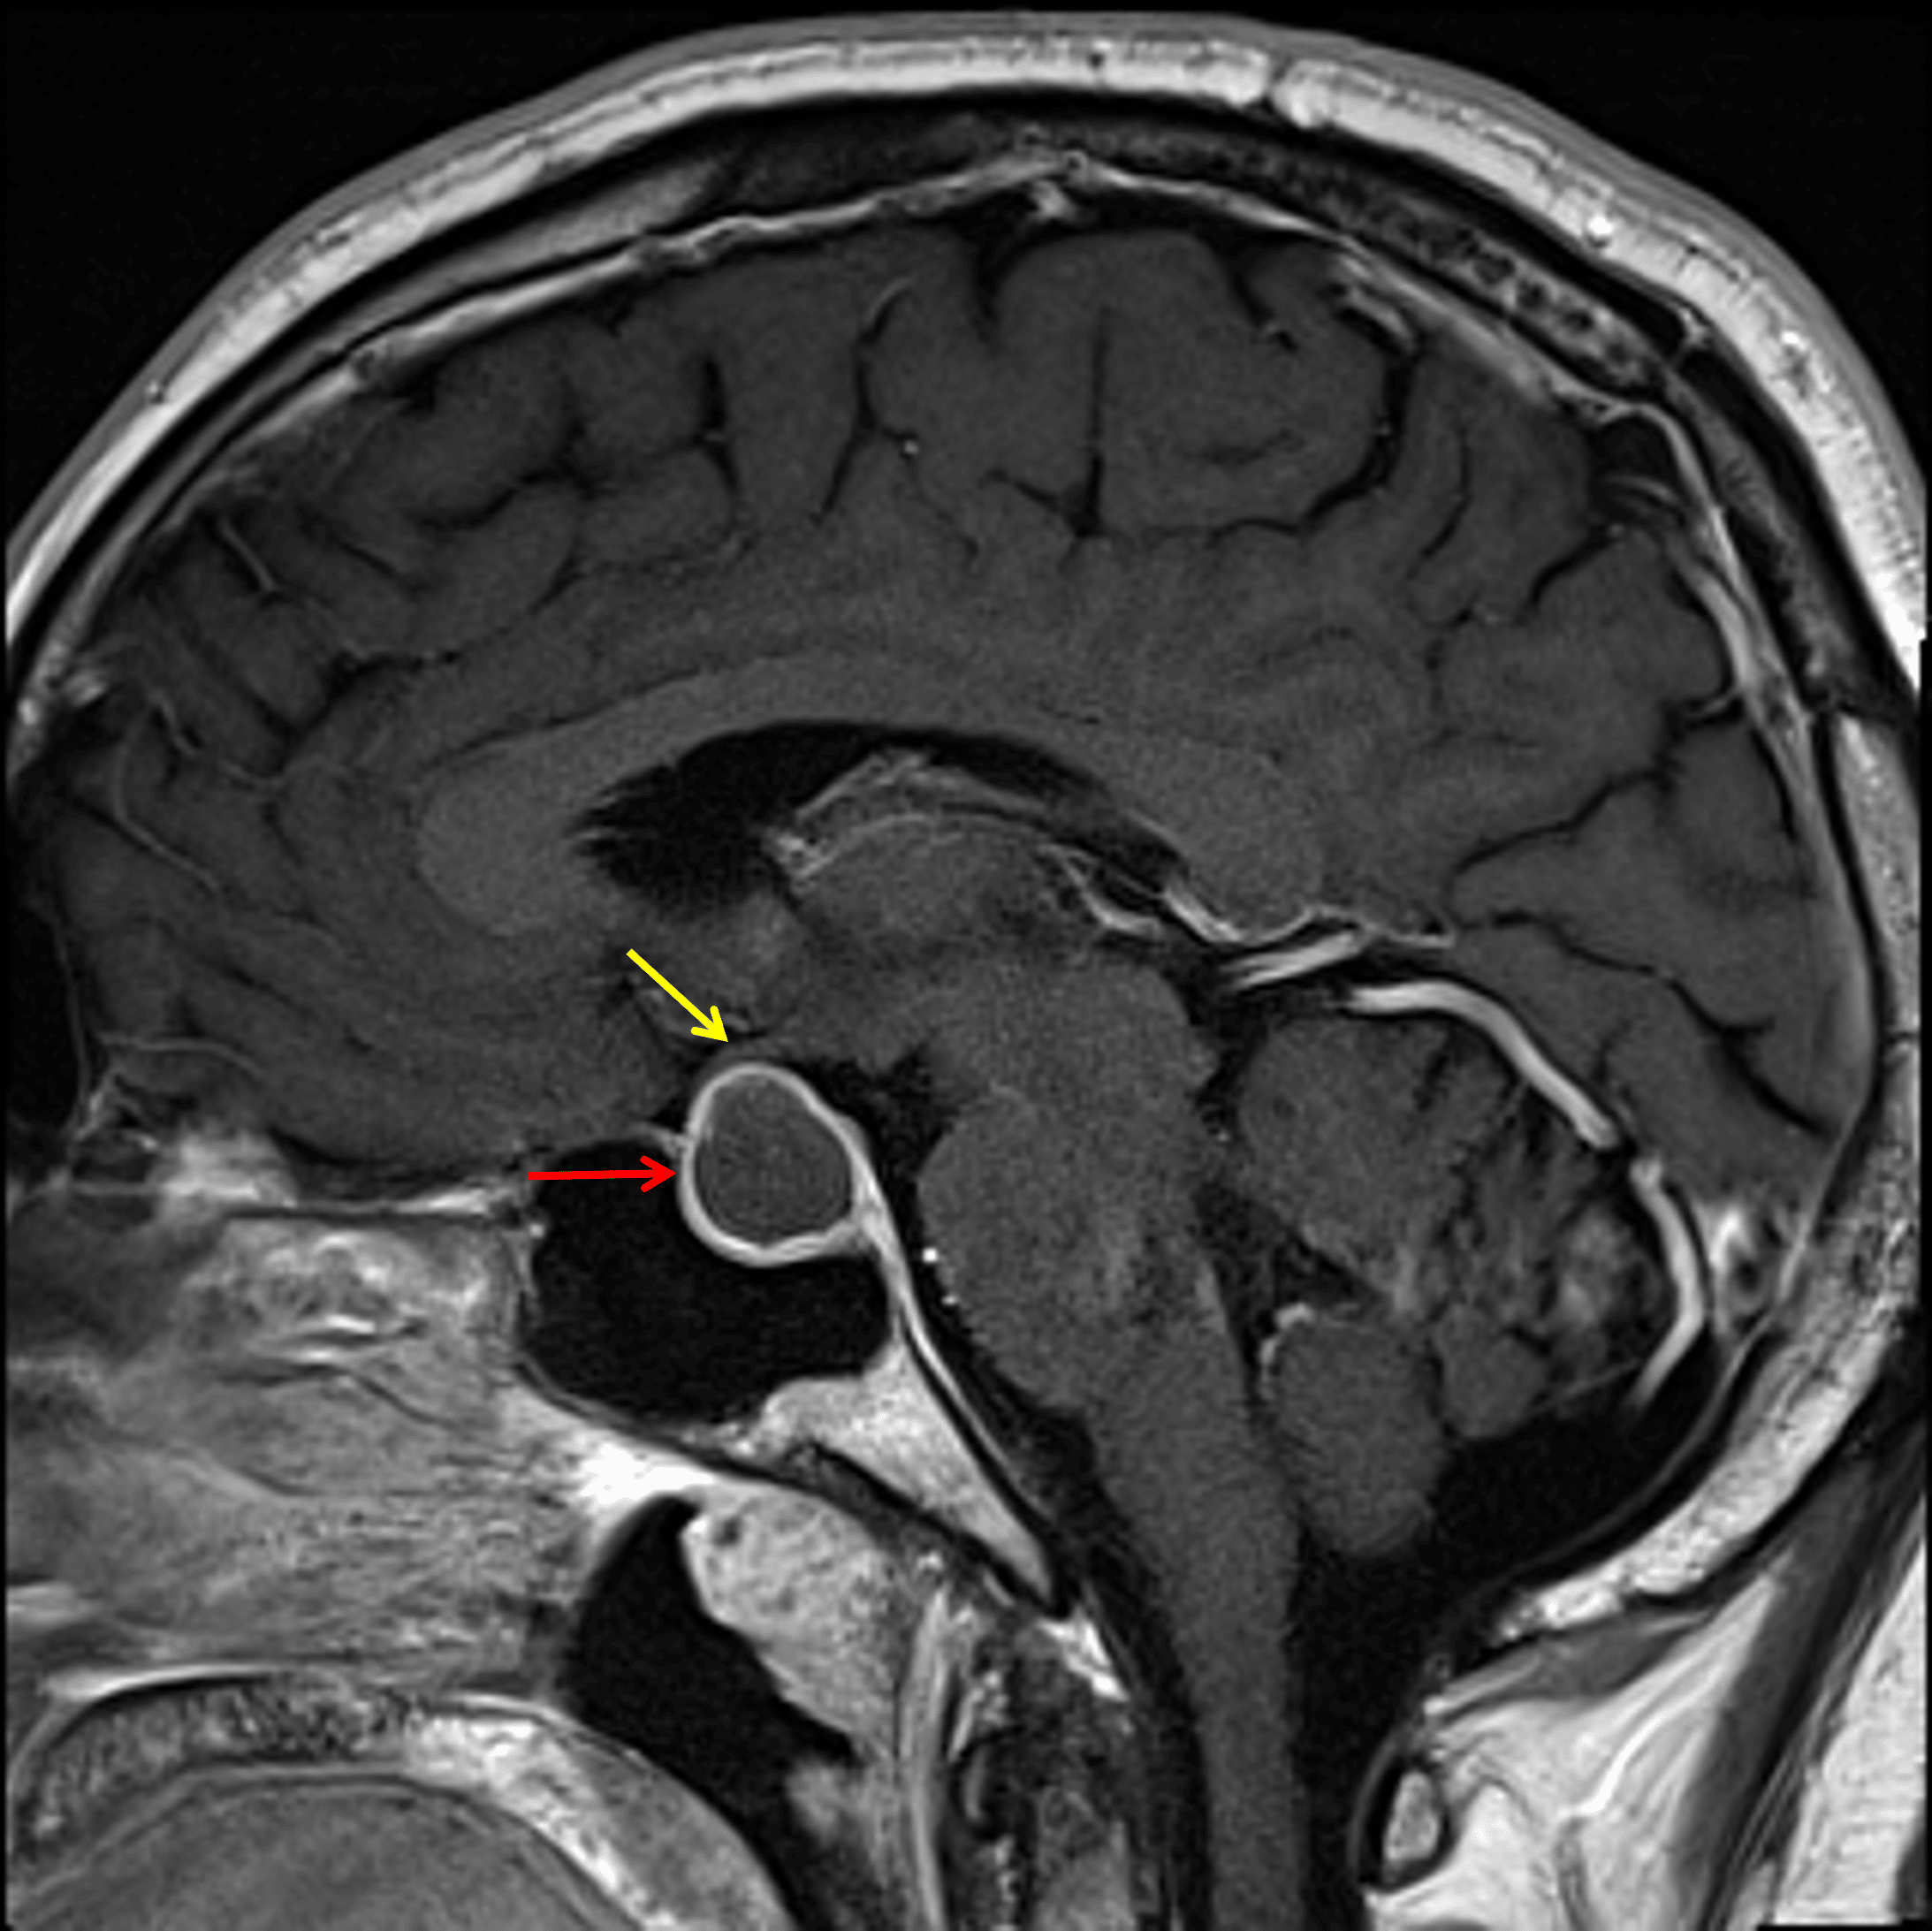

• The lesion contacts and mildly uplifts the optic chiasm

The lesion demonstrates peripheral enhancement (red arrow) and contacts and mildly uplifts the optic chiasm (yellow arrow).